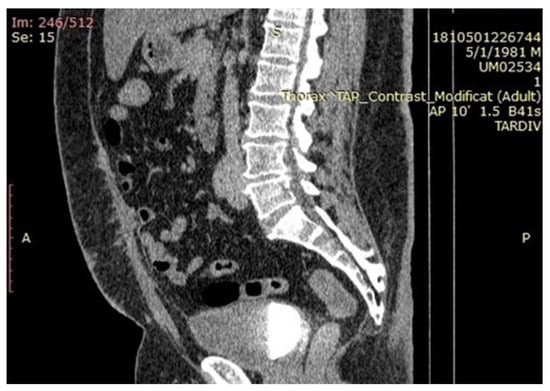

Cystoscopy detected mucosal erosion and excluded a potential invasion of the bladder. Furthermore, it revealed no bladder diverticulum. Pelvic Magnetic Resonance Imaging (MRI) showed a large cystic mass confined to the pelvis measuring 75/91/127 mm (AP/TR/CC). The complex cystic lesion extended from the umbilicus to the antero-superior dome of the bladder, on the trajectory of the medial umbilical ligament. The tumoral mass extended anteriorly to the plane of the rectus abdominal muscles, and the postero-lateral came into contact with some intestinal loops and a portion of the sigmoid colon. In the caudal portion the antero-superior wall of the bladder was imprinted by a parietal infiltrative nodular lesion (not exceeding the mucous layer), in hyposignal T1 and T2, with several areas in hypersignal T2 and STIR, without diffusion restriction and intense contrast and size of 27/31/29 mm (AP/TR/CC).The aspects might suggest an urachal cyst with milky transformation in the portion of the bladder dome. There were several nodes with a short infracentrimetric axis located external iliac and bilateral inguinal (Figure 2A–C).

Figure 2.

(A–C) Cystic lesion extended from umbilicus to antero-superior dome of the bladder, on the trajectory of the medial umbilical ligament (A,B) and with involvement of the antero superior bladder wall (C).

Radiologically, a diagnosis of urachal tumor with unknown malignant potential was put forth.